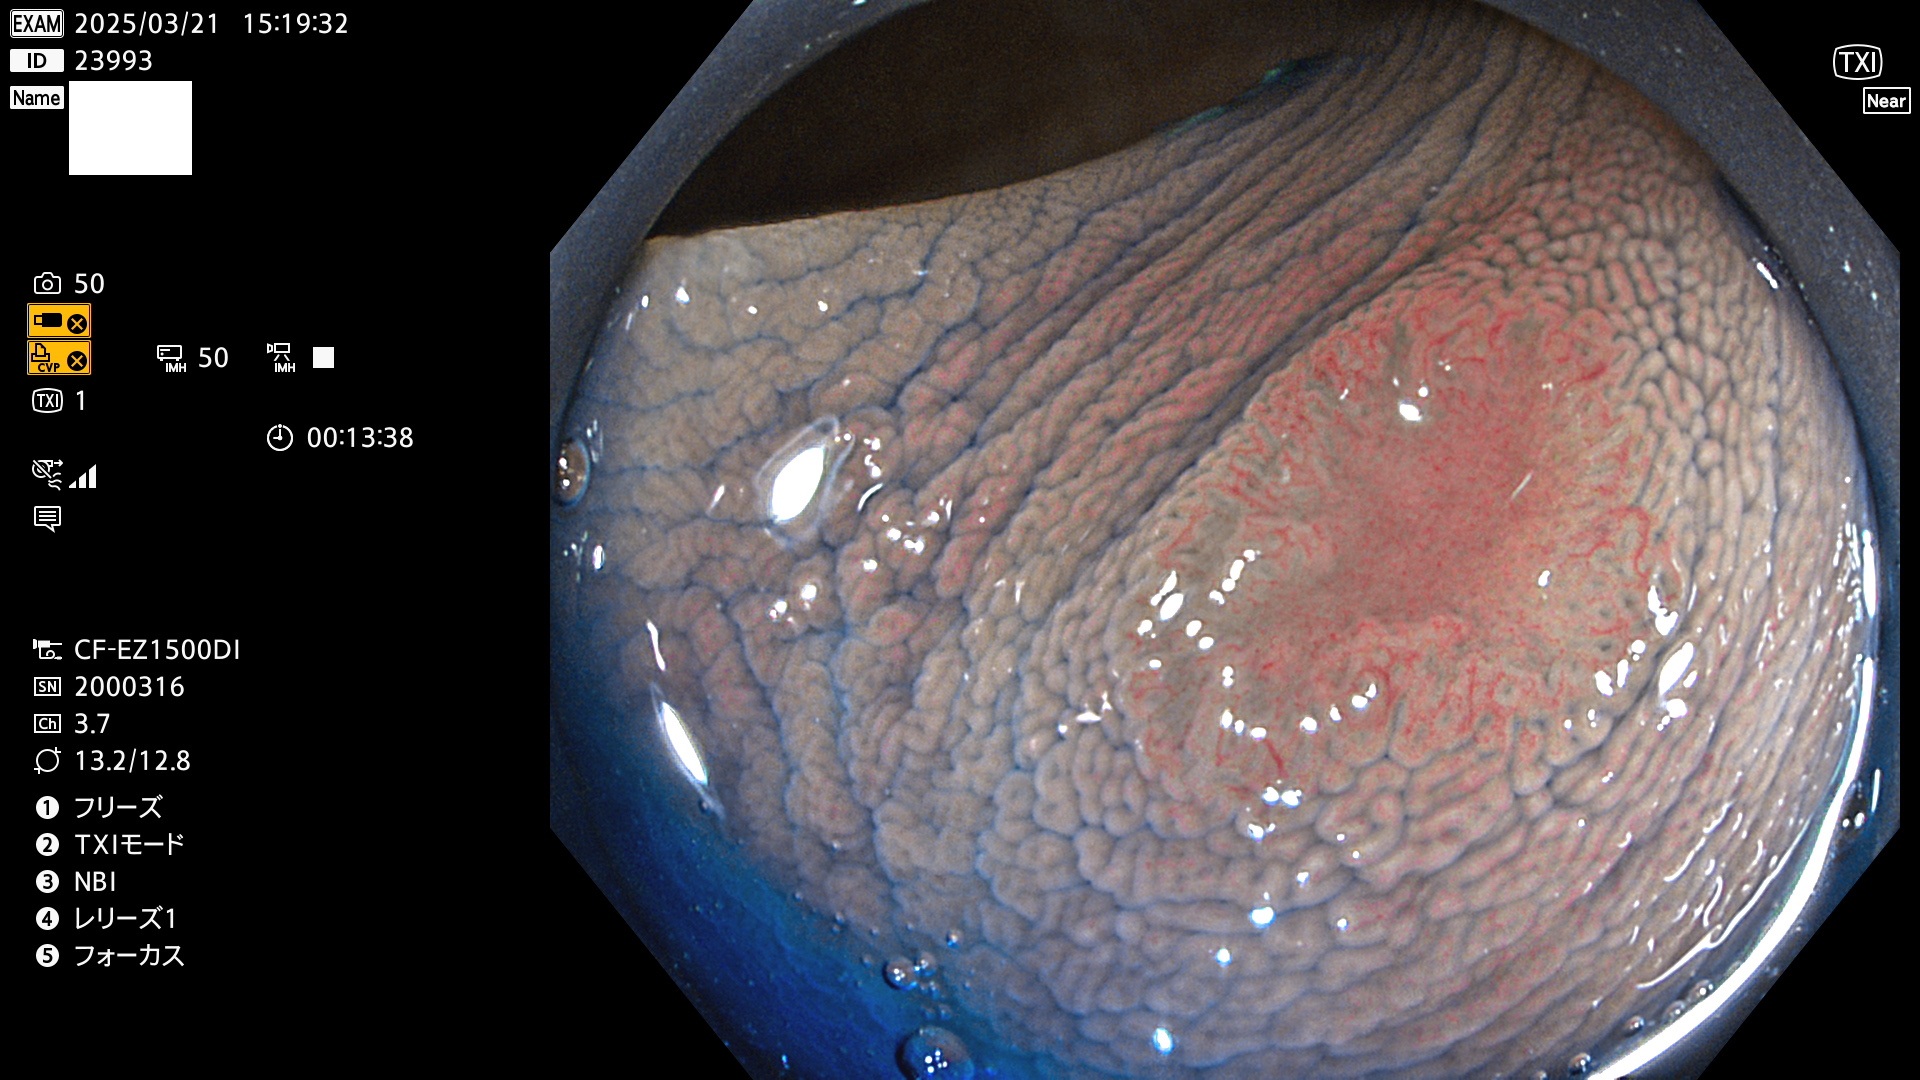

今週のUb、Uc型腺腫

完全に平坦な物をUb、陥凹している物をUcと呼びます。Ubは認識が困難で、Ucはびらん(炎症)と紛らわしいために見落とされやすく、「内視鏡後・大腸癌」の原因になります。

抽出の対象期間 2025年3月20日〜3月23日の4日間(48件の検査)10個 (10/48=21%)